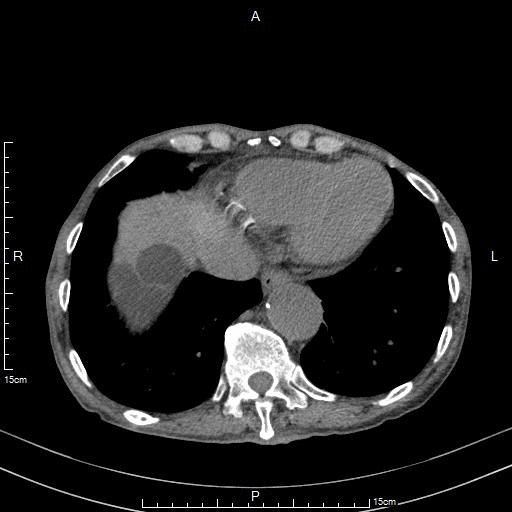

老年男性,腹部闷胀痛1年余。CT检查显示肝脏多发、巨大囊肿,最大者直径达20cm。患者行CT引导下肝穿刺置管引流及硬化治疗后,腹胀痛症状即刻缓解。

CT显示肝脏多发、巨大囊肿